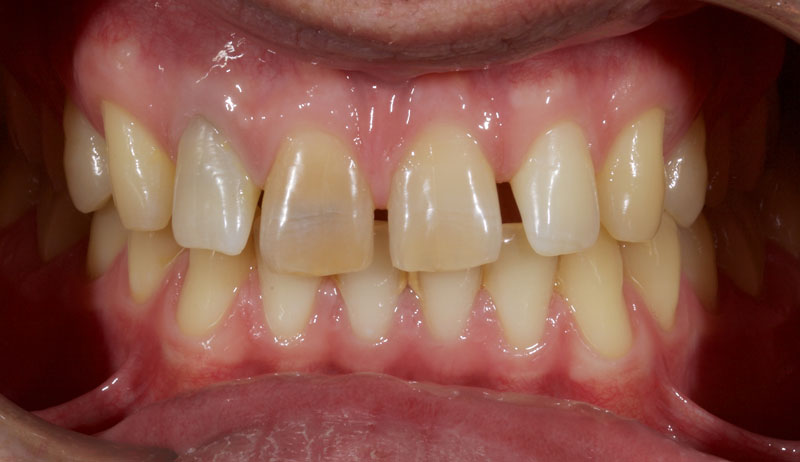

Treatment with direct resin is challenging due to the multiple diastemata and the potential risks of overhangs, defective contact points, and canted midlines. See Fig. 1 (before treatment) and Fig. 2 (after treatment).